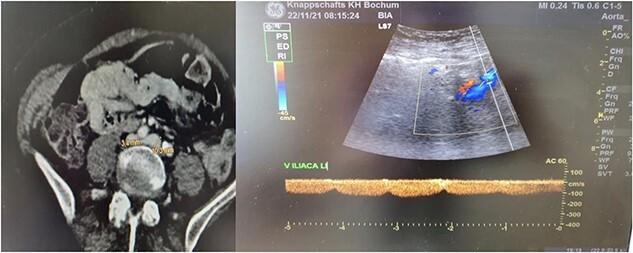

Common left iliac vein compression, otherwise known as May-Thurner Syndrome (MTS), is a medical condition that refers to chronic compression of an anatomical variant of the left iliac vein by the overlying right common iliac artery and is a predisposing factor for deep vein thrombosis of the left lower limb (LDVT). Although MTS is not often, its true prevalence is underestimated due to misdiagnose, fact that can result to life-threatening conditions such as the development of LDVT and pulmonary embolism. In this paper, we present a case of MTS presenting at our department with unilateral leg swelling without LDTV that was treated through endovascular management along with long-term anticoagulation. With this presentation, the authors wish to emphasise the importance of MTS as a frequently under-diagnosed condition that needs to be ruled out in unilateral left leg swelling with or without LDVT.

常见的左髂静脉受压,又称梅-图二氏综合征(MTS),是一种医学病症,指的是上方的右髂总动脉对左髂静脉解剖变异的慢性压迫,是左下肢深静脉血栓形成(LDVT)的一个诱发因素。尽管MTS并不常见,但由于误诊,其实际患病率被低估了,这一事实可能导致诸如LDVT和肺栓塞等危及生命的病症。在本文中,我们介绍了一例在我们科室就诊的MTS病例,该病例表现为单侧腿部肿胀但无LDVT,通过血管内治疗及长期抗凝进行了治疗。通过此病例展示,作者希望强调MTS作为一种经常被漏诊的病症的重要性,在单侧左腿肿胀伴或不伴LDVT的情况下都需要排除该病症。